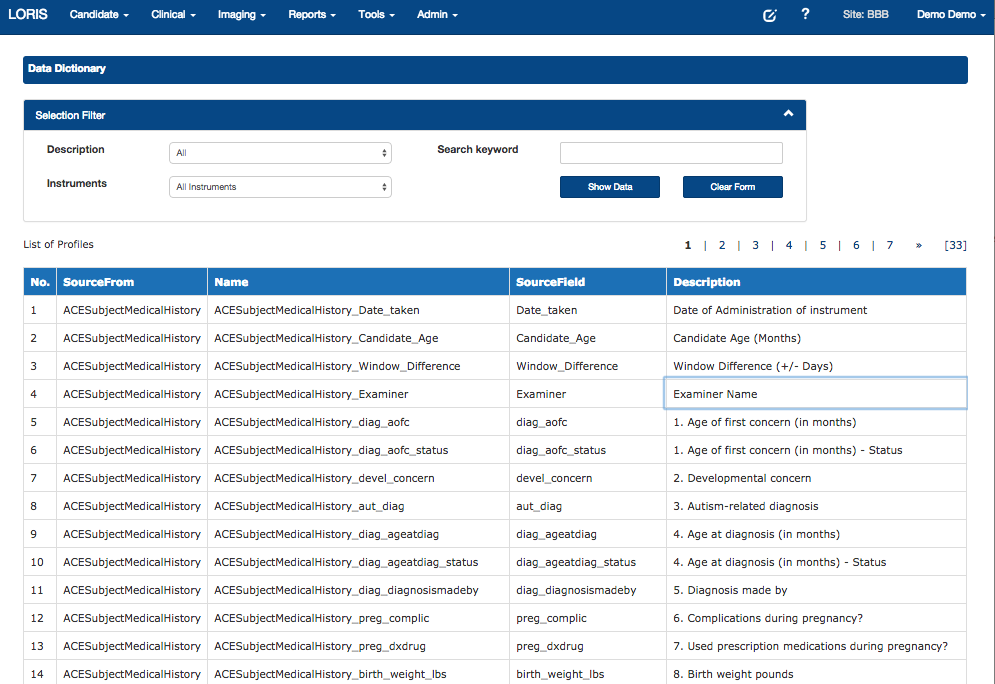

Data Dictionary Builder

Data Querying Tool